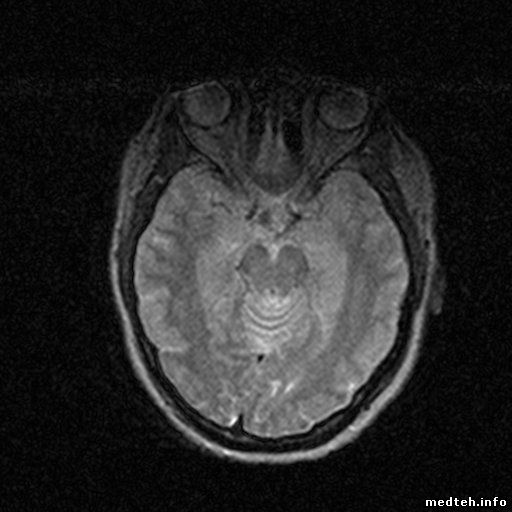

Доброго времени всем, помогите пожалуйста разобраться с чудом китайского мед. прома. Аппарат перестал выдавать читаемую картинку, пропала детализация и контраст +картинка стала шумновата, подскажите в какую сторону смотреть? Мануалов нет, из того что знаю по нему подстраивал offs на градиентах (на картинку не влияет).

7558872.jpg (38.7 Kb) · 5127933.jpg (31.7 Kb)